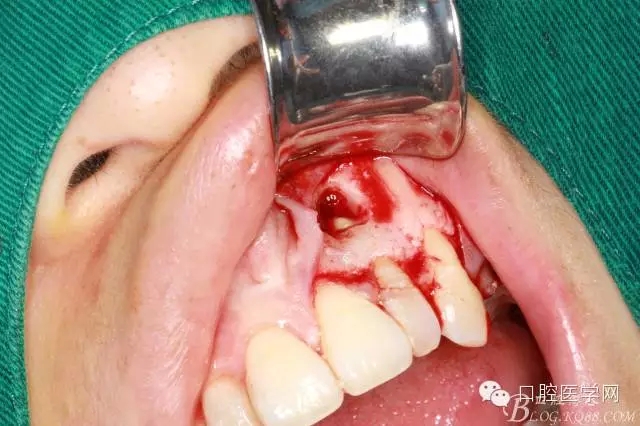

繼續(xù)去骨暴露牙根

牙根露出3mm左右因為根切長度

沖洗干凈開窗處

根切后可見開窗處清理干凈

刮出囊腫及牙根2.5MM

填明膠海棉(建議植骨和應(yīng)用生物膜)患者不同意因費(fèi)用較高

復(fù)位縫合

填塞牙周塞治劑